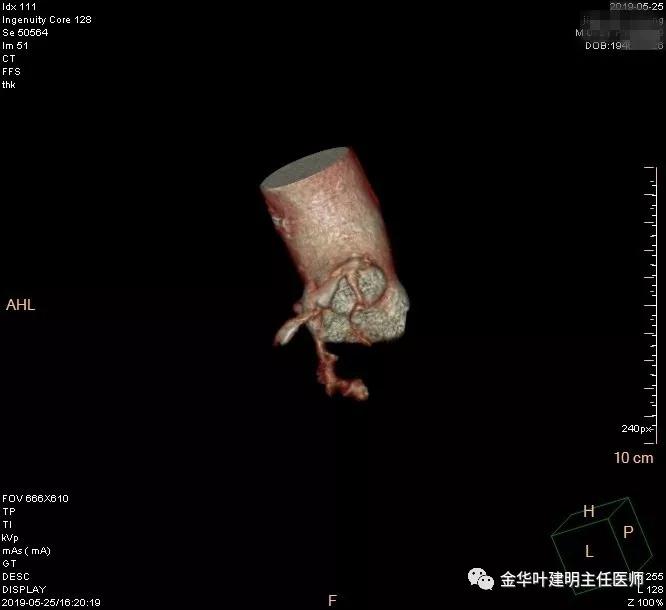

术前检查冠脉CT示:左冠前降支近段多发钙化斑块伴管腔重度狭窄(约85%),建议DSA检查。但追问病史以往平时无胸痛或胸闷症状,运动试验提示可疑阳性(上斜型压低),活动后胸闷气闭症状不明显,既往否认高血压、糖尿病。所以经过心内科会诊讨论,认为还是可以进行手术。术前冠状动脉CT示: